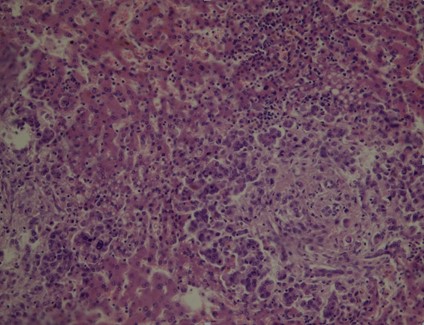

Volver a los detalles del artículo Linitis plástica gástrica